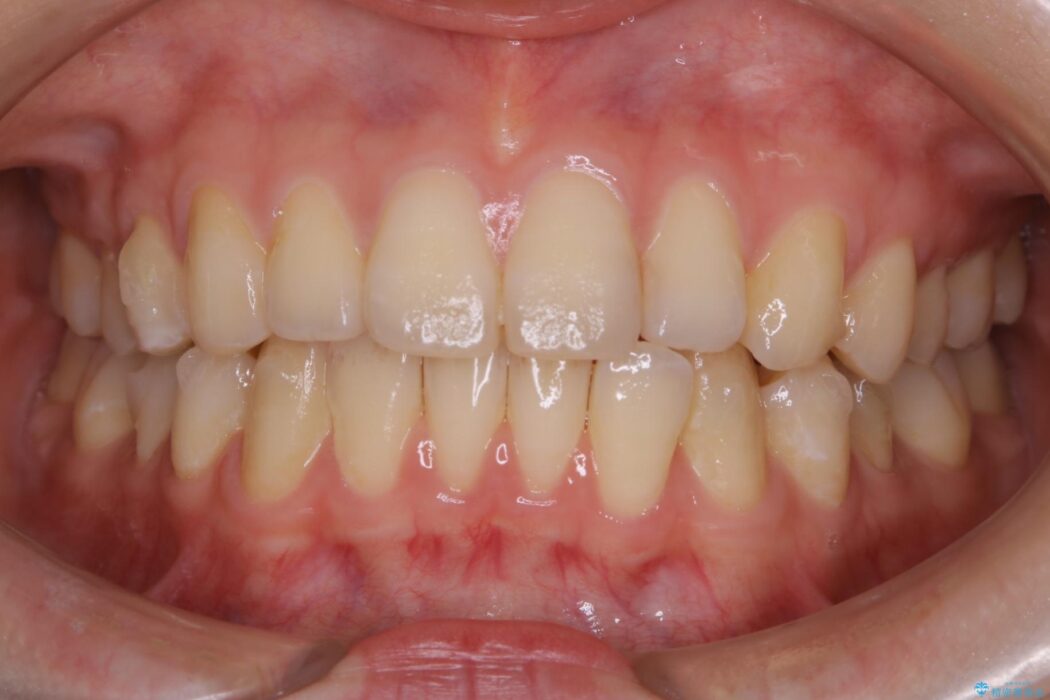

下の前歯のガタつきが気になるとご来院された患者様です。

インビザラインのライトパッケージにて、歯列拡大とディスキング(IPR)をを行いスペースをつくり非抜歯で治療を行いました。

ディスキング(IPR)

歯のガタつきをとるためのスペース作りの方法の一つにディスキング(IPR)という方法があります。

歯と歯の間を一ケ所あたり最大0.5mmまでの範囲内で削ることで歯自体が少し小さくなり、それにより作られるスペースを数ヶ所分合わせることで合計で数mmの大きなスペースが作れるという方法です。

当院ではなるべく歯の機能や見た目に影響の出ないよう、作業時に拡大鏡の使用や削るタイミングの微調整を行っています。